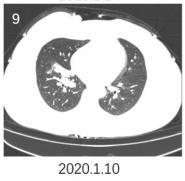

▎流感

流感,特别是甲流,也会表现为胸膜下为主的磨玻璃,但是出现的几率小于新冠肺炎。

下面的患者,就是甲流病毒性肺炎。